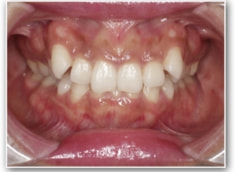

治療後